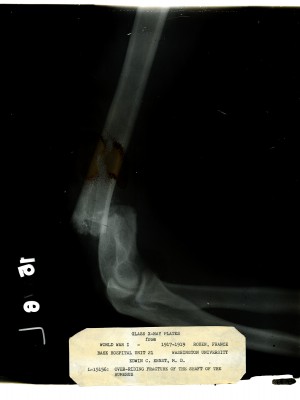

Dr. Edwin Ernst, an only child born to St. Louis residents Charles and Catherine Ernst, was a notable Roentgenologist, a physician who specializes in radiological work. Dr. Ernst studied at Washington University in St. Louis and later at Moravian College in Bethlehem, Pennsylvania earning his advanced degrees. For two years he served as a resident physician at the St. Louis Mullanphy Hospital before leaving to pursue a private practice. When the United States formally entered the war in 1917, Ernst left St. Louis to become chief radiologist at Base Hospital 21. He was discharged honorably in 1919 with the citation of Major. His collection consist of x-ray images taken at Base Hospital 21 as well as drawings of radiological equipment and photographs.